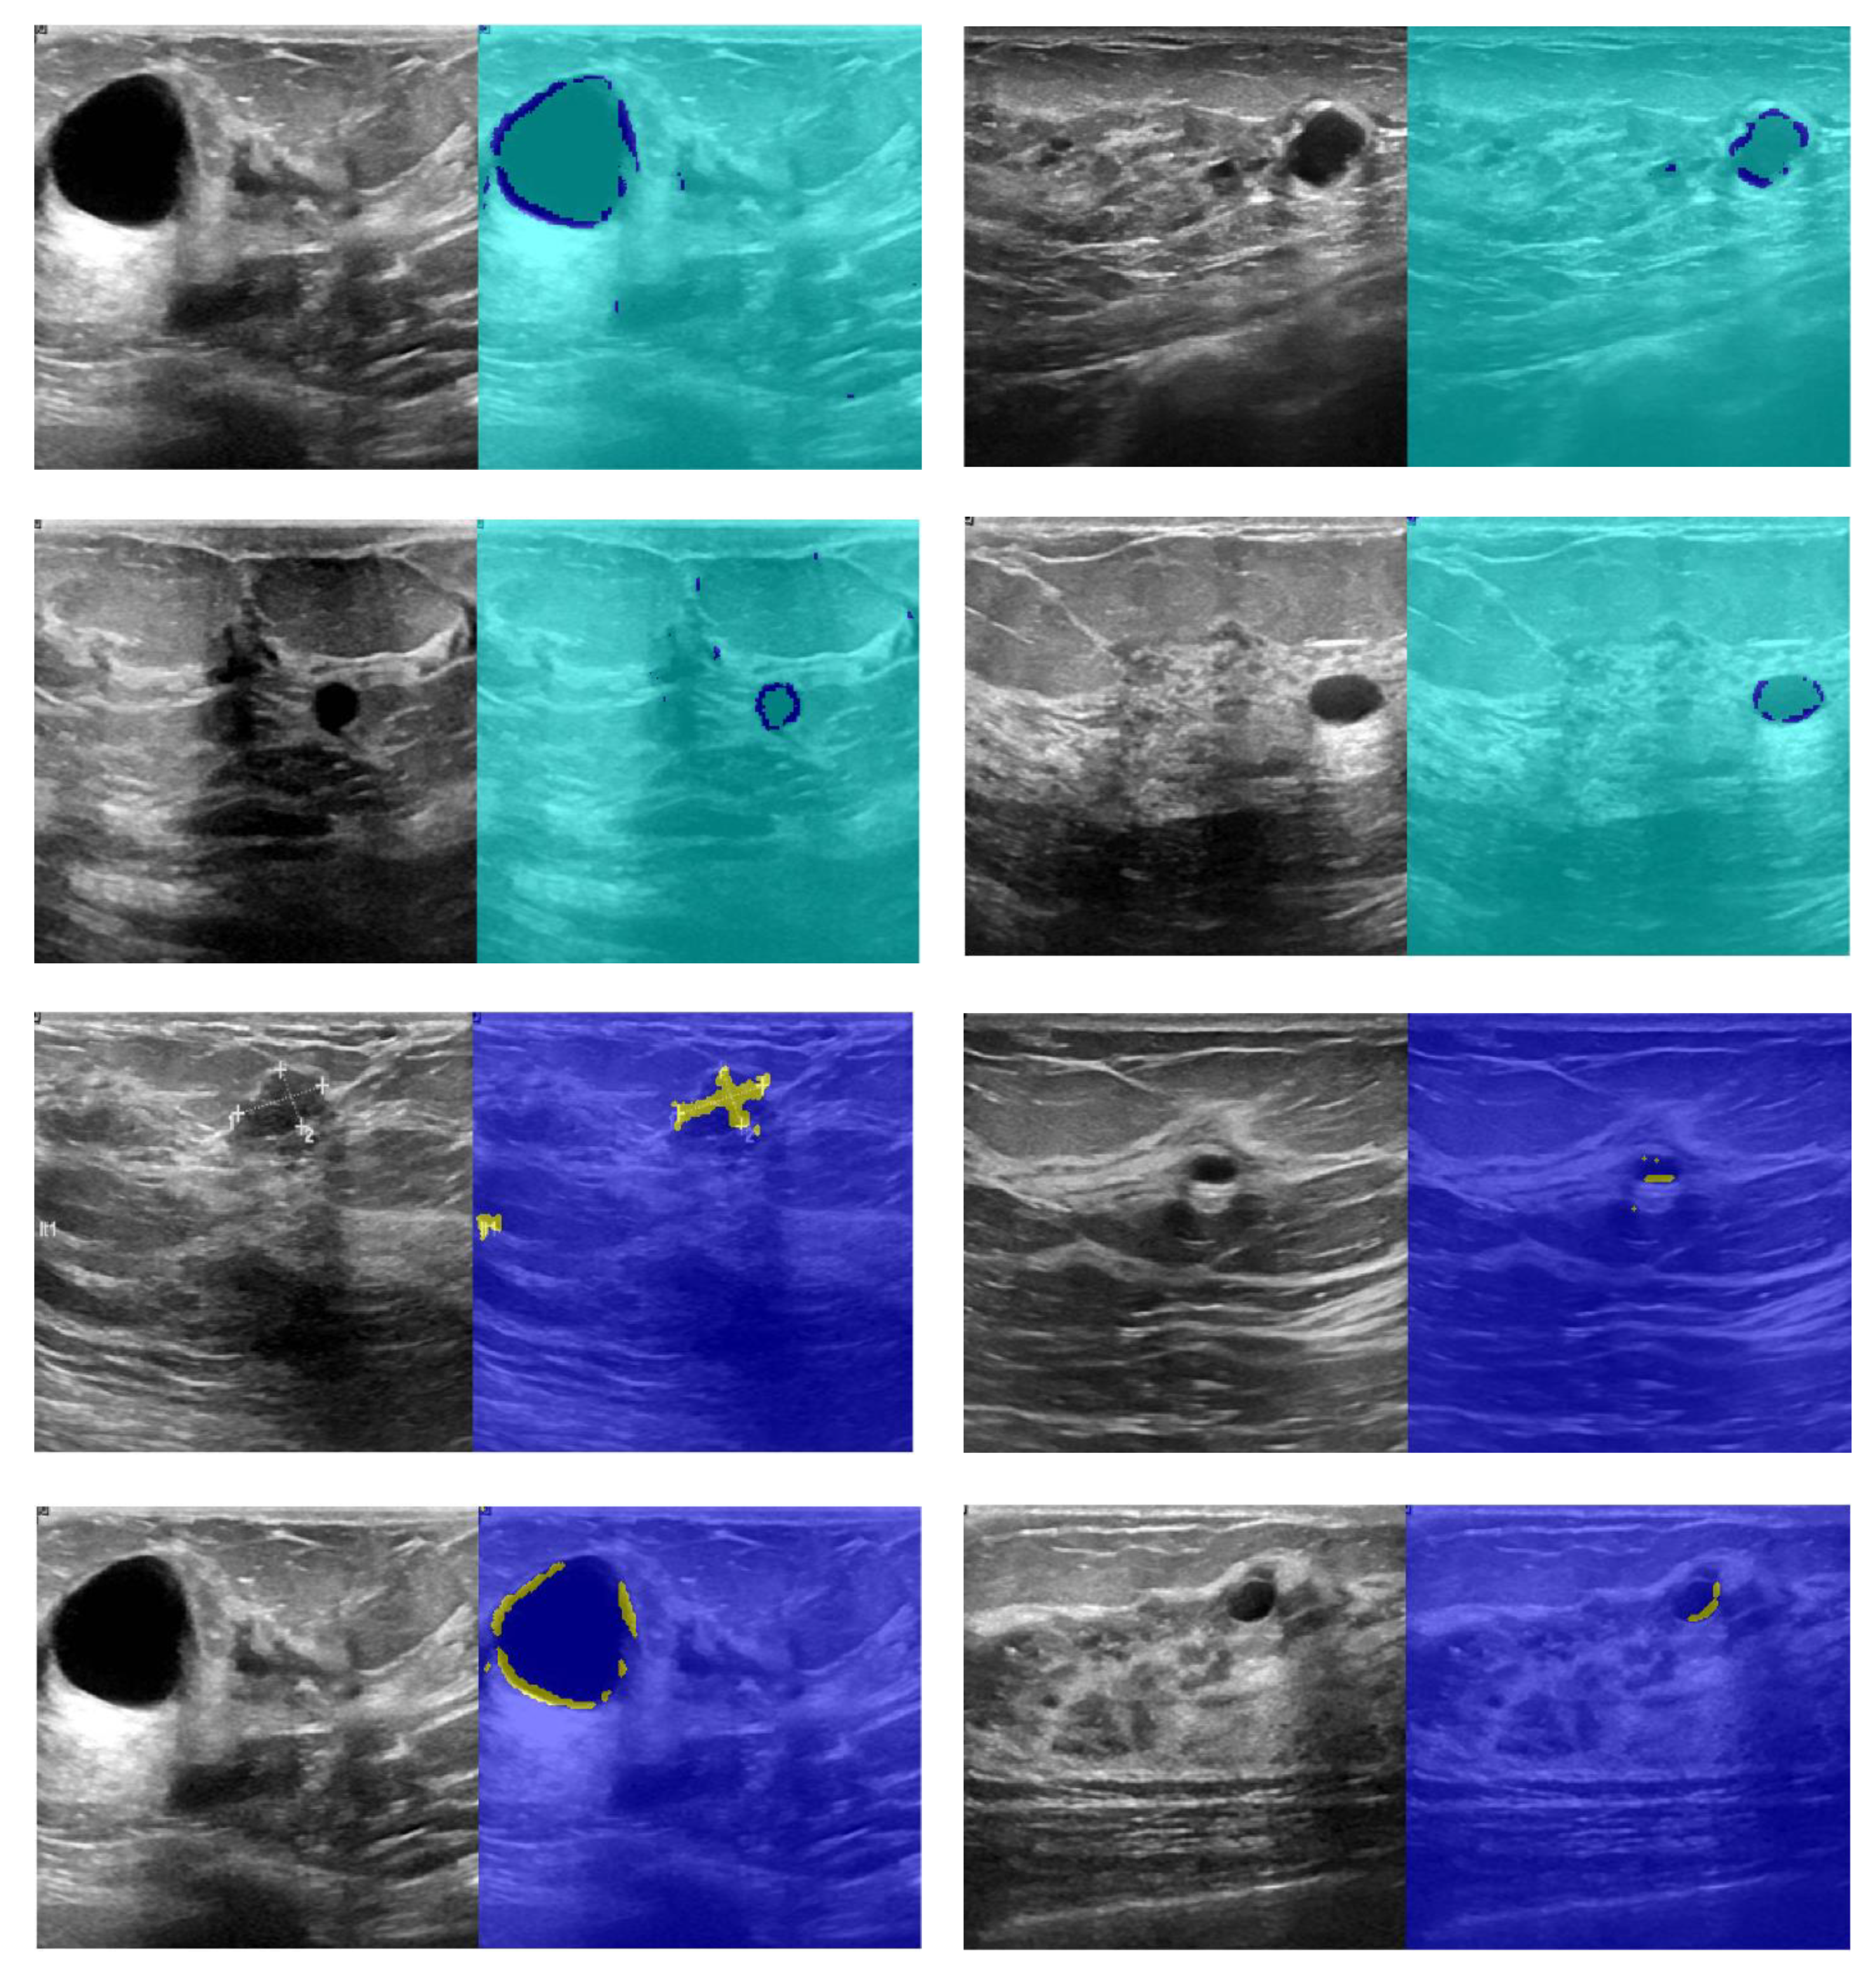

4.6. Segmentation of Ultrasound Images Using the Presented CNN